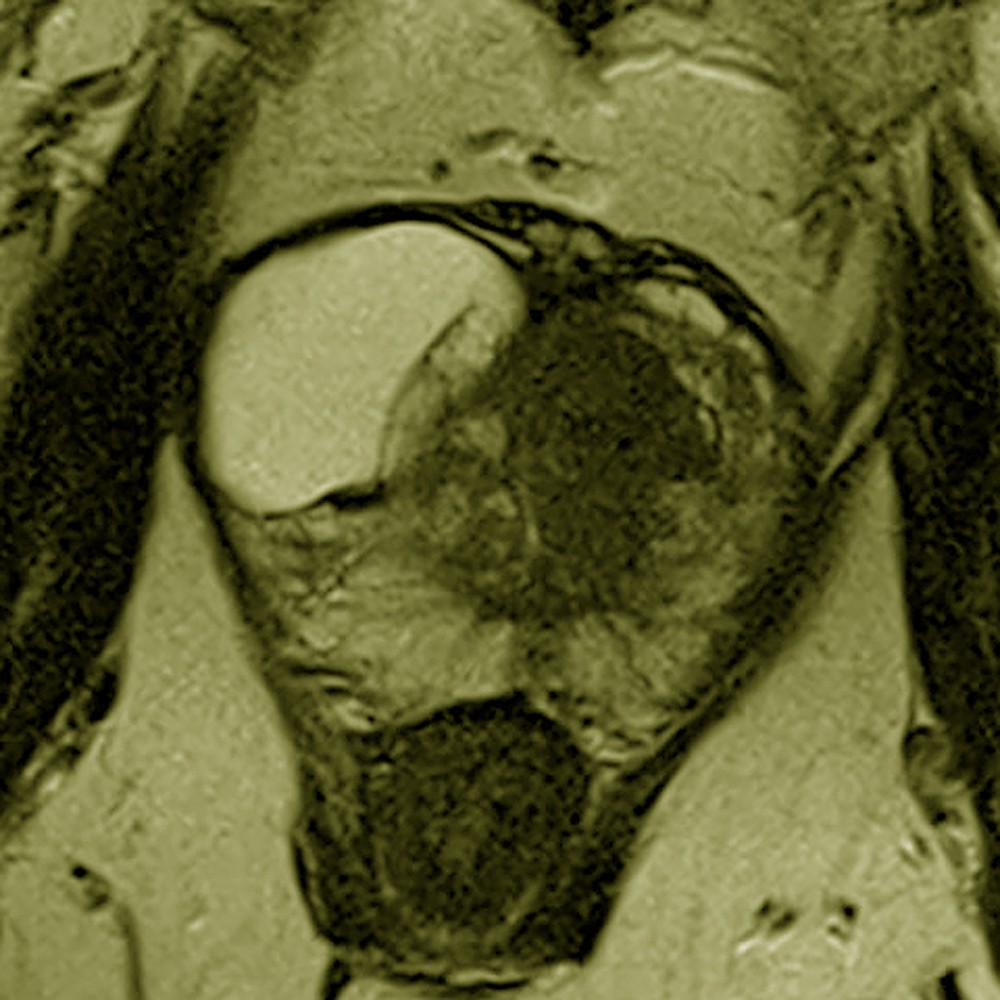

Willkommen zum 16. Petersberger Symposium – dem zentralen Treffpunkt für Expertinnen und Experten der klinischen Radiologie. Unter dem Motto „Radiologie meets Urologie“ widmen wir uns 2026 der Zukunft des Prostata-Screenings: von technischer Innovation über künstliche Intelligenz bis hin zu neuen diagnostischen und therapeutischen Standards.

Präzise Diagnostik und Biopsie im Wandel

• Fortschritte in der MRT-basierten Diagnostik

• Bildgeführte Biopsieverfahren